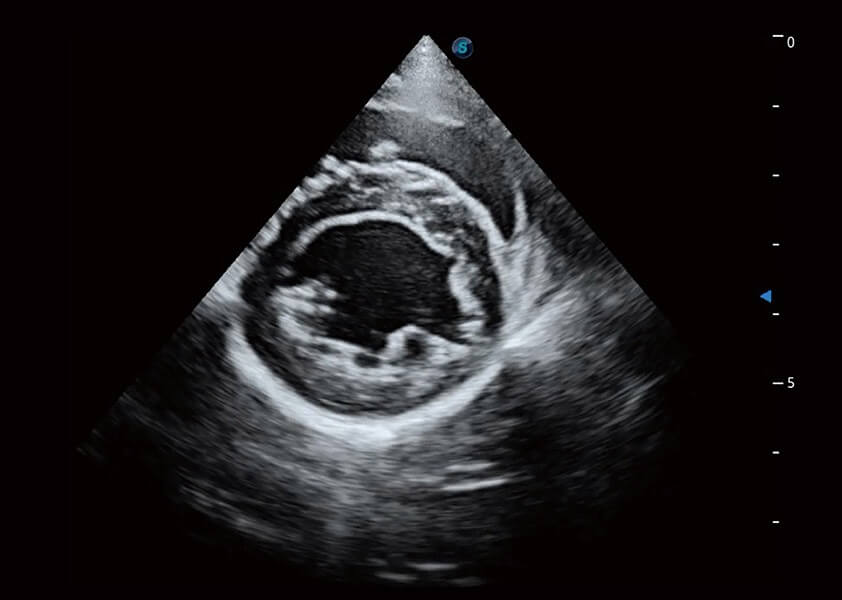

ProPet 60 作为一款高端台式动物超声设备,为动物医生的日常诊断提供了一系列贴合动物临床需求、解决临床实际问题的高级成像功能。凭借全系列高清探头,满足医生对腹部、心脏、生殖、浅表、肌骨等成像的所有需求,切实帮助您提升检查效率,提高诊断信心。

兽用彩色多普勒超声诊断系统

动物是人类最亲密的朋友和最值得信赖的伙伴。乐玩lewin国际也一直致力于探索动物专用的超声影像解决方案。 全新推出的ProPet系列,是乐玩lewin国际在动物超声影像智能化、专业化、精准化的一次跨越式革新。动物不能用言语来表述自己的不适,通过超声影像,ProPet系列搭建了动物医生与不同物种沟通的“桥梁”,为动物医生注入了“治愈之力”。